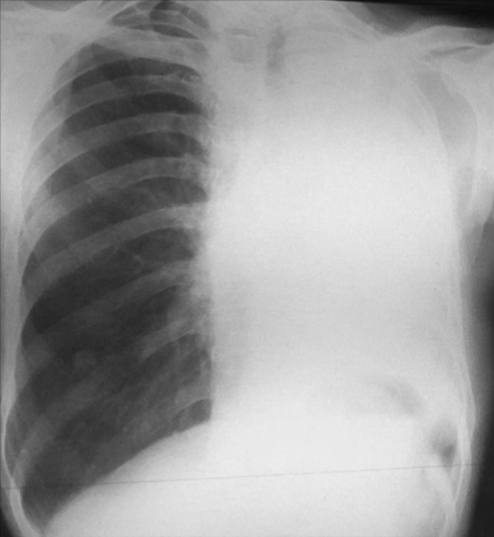

Rx toracică, incidență P-A

DESCRIERE:

la niv. întregului hemitorace stg → opacitate extinsă, nesistematizată, de intensitate mare, omogenă

caracter retractil → tracționează traheea și mediastinul de partea afectată

fără bronhogramă aerică

duce la micșorarea spațiilor intercostale

la niv. hemitoracelui controlateral → hipertransparență compensatorie

DX: atelectazie prin NBP central endobronșic (pe bronhia principală stg)

DD: pleurezie masivă → caracter expansiv